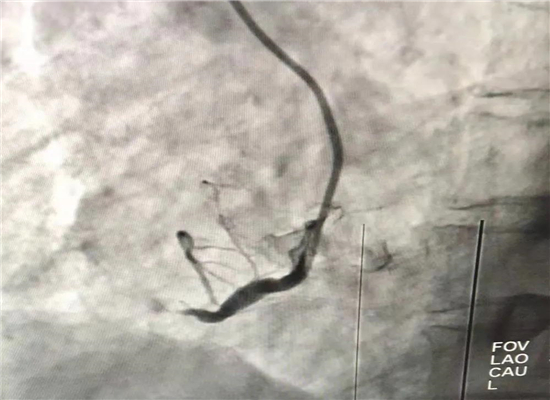

19时13分左右,一名患者因晚饭后行走不稳而请求出诊,急诊医学科医护人员火速赶往现场,到诊时测生命体征,输液后接回急诊医学科,回科后做心电图检查,诊断为急性心肌梗塞,随即通知心血管内科会诊,确定做急诊介入治疗,20时30分进入导管室,杨勇主任、张轩副主任共用21分钟就实现了心肌再灌注,挽救了患者生命。

介入手术前